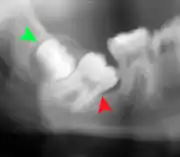

Impacted 2nd molar (red arrow) with developing wisdom tooth (green arrow)

There is no standard to screen for wisdom teeth. It has been suggested, absent evidence to support routinely retaining or removing wisdom teeth, that evaluation with panoramic radiograph, starting between the ages of 16 and 25 be completed every 3 years. Once there is the possibility of the teeth developing disease, then a discussion about the operative risks versus long-term risk of retention with an oral and maxillofacial surgeon or other clinician trained to evaluate wisdom teeth is recommended. These recommendations are based on expert opinion level evidence.[19] Screening at a younger age may be required if the second molars (the "12-year molars") fail to erupt as ectopic positioning of the wisdom teeth can prevent their eruption. Radiographs can be avoided if the majority of the tooth is visible in the mouth.